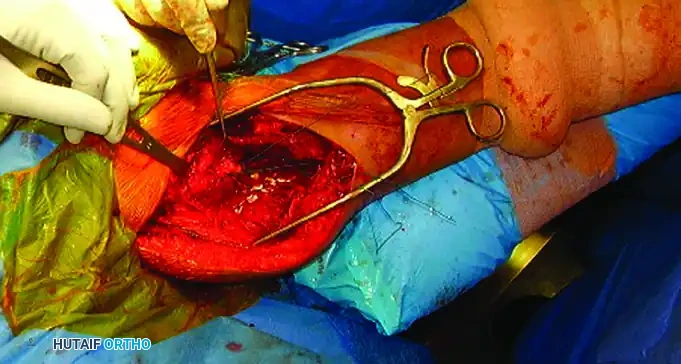

- Tuberosity Control: Place heavy, non-absorbable sutures (e.g., #2 or #5 FiberWire) through the rotator cuff tendons at their insertion sites on the greater and lesser tuberosities. These sutures act as traction tags to manipulate the tuberosity fragments out of the subacromial space and reduce them to the shaft.

Open reduction and internal fixation of a proximal humeral shaft fracture. Sutures placed in the rotator cuff are actively used to assist in the reduction of the tuberosities.

Sutures utilized for the precise reduction and provisional fixation of comminuted tuberosity fragments.

Clinical photograph demonstrating the proximal exposure. The plate is prepared to be slid distally beneath the axillary nerve.

The plate is successfully secured to the humeral shaft. The axillary nerve is clearly visible, safely crossing over the plate at the head-shaft junction.